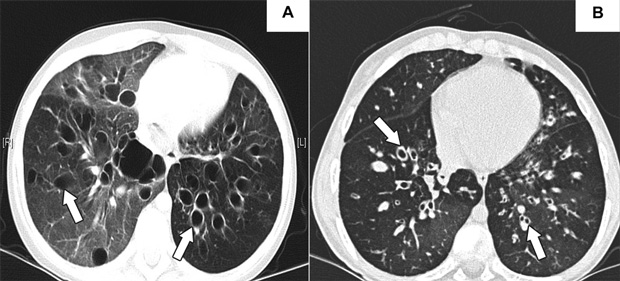

A previously healthy 9-year-old girl presented in early 2007 with an upper respiratory tract infection that progressed over 10 days to respiratory failure, requiring intubation and ventilation with high inspiratory pressures. Subsequent tracheal aspirates were positive for Mycoplasma (by polymerase chain reaction), with consistent serological results (antibody titres, 1 : 640). Computed tomography of the chest demonstrated widespread bronchiectasis (Box 1, A). Although she was extubated 6 weeks after initial presentation, she remained in hypercapnic respiratory failure (Pco2, 80 mmHg), requiring continuous oxygen supplementation (5 L/min) and bilevel non-invasive positive-pressure ventilation (BiPAP). She was listed for lung transplantation in May 2007, but, given the severity of her lung disease and in the absence of appropriately matched donor organs, the transplant team gave early consideration to cadaveric bilateral lobar transplantation using an adult “oversized” donor. This was performed in August 2007.

A 13-year-old girl with cystic fibrosis was referred for consideration of lung transplantation. She had been diagnosed with cystic fibrosis at birth (Δ508 homozygous, without liver, sinus or diabetic sequelae), and over the preceding 2 years developed progressive bronchiectasis (Box 1, B), necessitating supplemental oxygen and initiation of nocturnal BiPAP. She was initially listed for either lung transplantation or heart–lung transplantation; however, after 9 months of progressive respiratory failure (Pco2 increased to 46 mmHg; forced expiratory flow in 1 second [FEV1], 16%; forced vital capacity [FVC], 28% predicted), the transplant team considered cadaveric bilateral lobar transplantation, which was performed in September 2007.